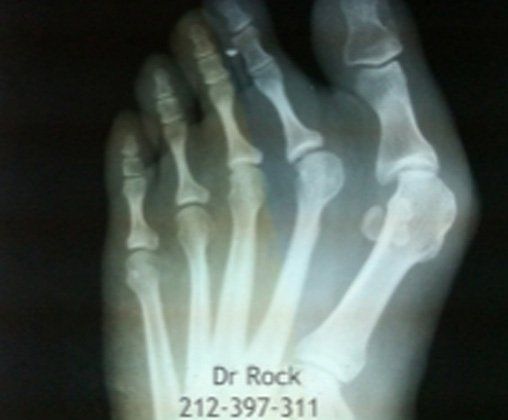

Get Beautiful, Pain-Free Feet

Take a look at our x-ray pictures of our recent footwork and see how your feet can benefit.

Whether you want to improve the look of your feet or need to relieve pain,

you can find out the best option for you with our FREE phone consultation.